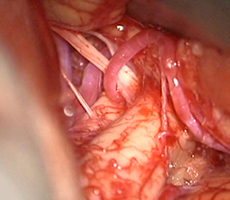

実際の手術所見

クリップ留置(瘤の消失:赤矢印)

手術中の脳血管撮影画像

クリップ留置後、瘤(こぶ)は消失 -

(手術後) -

患者様は術前からあった左視力低下以外に神経症状なし。元気に自宅退院されました。